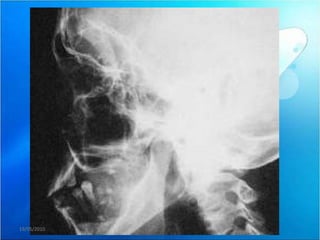

b) BLOQUEO ABIERTO O LUXACION

 Situación clínica en la que el cóndilo está

posicionado por delante de la eminencia

articular y no es capaz de volver a su posición

inicial (boca cerrada) debido al espasmo de la

musculatura masticatoria.